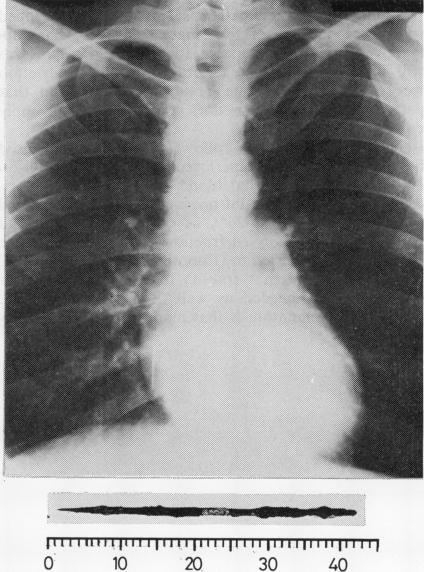

Constrictive pericarditis resulting from the transpulmonary migration of an inhaled nail.

Thorax. 1979 Aug;34(4):559-60. doi: 10.1136/thx.34.4.559.